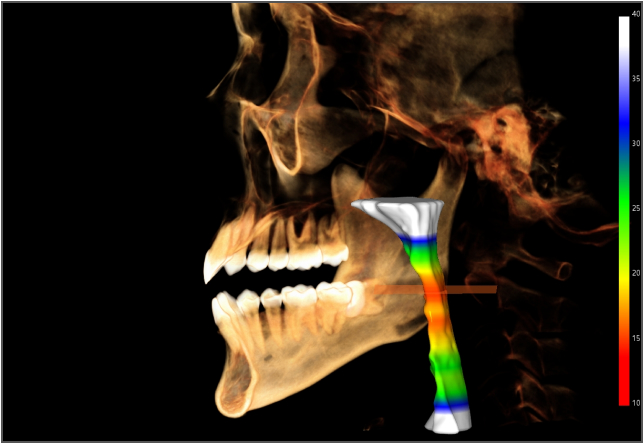

• lamtau AI氣道分析

AI氣道分析